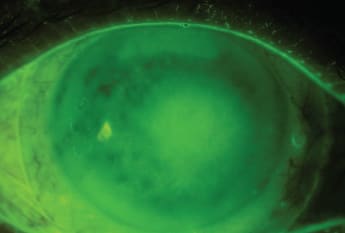

The major advantage of large-diameter GPs over the smaller lenses is certainly the initial comfort that they provide to patients (Segal et al, 2003). Because large-diameter GP lenses do not touch the cornea (Figure 1), they do not affect this very sensitive tissue. This is also a reason to not fit corneo-scleral lenses, a topic that will be discussed later in this article. Large-diameter GPs do not move on the eye, thus limiting the interaction between the lens and the lids (with smaller GP lenses, this interaction is the main cause of long-term discomfort). Because of a large-diameter GP’s fluid reservoir, the cornea and part of the ocular surface remain bathed in fluid during all wearing hours, thus alleviating ocular dryness (Alipour et al, 2012), end-of-day dryness, and problems related to lens dehydration with wear. Consequently, once fitted properly, large-diameter GP lenses are initially and over the long term as comfortable as soft lenses are (Michaud et al, 2012). In fact, when patients report discomfort, it is typically an indication that the large-diameter GP fit is not optimal.

Figure 1. An optical coherence tomography view of a scleral lens vaulting over the cornea.